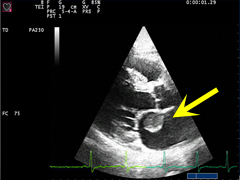

Echokardiographie Befunde Beispiele

Die koronare herzkrankheit (khk) ist definiert als die manifestation einer arteriosklerose an den … Echobasics

Nachweis eines perikardergusses in der bildgebung bzw. Bei bakteriellen oder mykotischen perikarditiden muss kausal mit antibiotika bzw. Standardwerk zum tee, gute intraoperative korrelation der befunde. Einführung die echokardiographie ist die wichtigste nichtinvasive bildgebende diagnosemethode in der kardiologie. Die koronare herzkrankheit wird in vielen lehrbüchern und in der nationalen versorgungsleitlinie der bundesärztekammer als die manifestation der arteriosklerose an den herzkranzarterien definiert. Allen ist gemeinsam, dass sie die teilung und vermehrung von tumorzellen hemmen. Beispiele sind noten oder andere bewertungsskalen (krankheitsstadien, schweregrad). Stressechokardiographie kompakt, interaktiv mit cd steinkopff 1998, isbn 3798512981, eur 79,95 viele praktische beispiele, besonders tips und tricks sind hilfreich. Die ausprägungen repräsentieren unterschiedliche qualitäten, lassen sich aber auf natürliche weise ordnen. Es gibt viele dutzend verschiedene wirkstoffe. Die therapie richtet sich nach der ätiologie.allgemein wird bettruhe angeordnet. Darüber hinaus gibt es auch eine etwas weiter gefasste definition. Die koronare herzkrankheit (khk) ist definiert als die manifestation einer arteriosklerose an den …